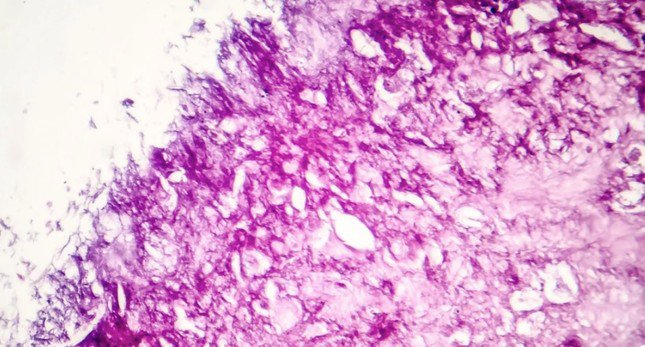

Các nhà khoa học ở Mỹ vừa tìm ra phương pháp tiêu diệt tế bào ung thư bằng cách dùng ánh sáng cận hồng ngoại để kích thích phân tử, khiến chúng rung lên.

Phương pháp dùng ánh sáng cận hồng ngoại để làm rung phân tử có thể tiêu diệt 99% tế bào ung thư. (Ảnh: Euro News)

Họ phát hiện ra phương pháp này có hiệu quả 99% đối với tế bào ung thư ác tính nuôi cấy trong phòng thí nghiệm. Phương pháp của họ là làm rung động phân tử được nhuộm đỏ bằng ánh sáng cận hồng ngoại.

Nó tạo thành thứ gọi là plasmon, nghĩa là sự dao động nhanh của các electron trong phân tử giống như cách chuyển động của sóng biển. Điều này làm cho màng tế bào ung thư bị vỡ.